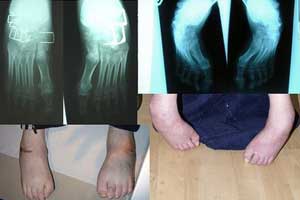

Первые симптомы заболевания появляются, как правило, в детском и подростковом возрасте. Пациенты жалуются на неуверенность во время ходьбы, шаткую походку. Затем появляется тремор и нарушается координация движений рук, изменяется почерк. При дальнейшем прогрессировании болезни развиваются мышечная слабость, нарушения слуха, зрения и речи, парезы. На развитых стадиях болезни отмечаются эндокринные нарушения, кардиопатологии, деформации костей.

Для коррекции развившихся дефектов кости, а также предупреждения сколиоза и препятствия прогрессированию патологии назначаются оперативные вмешательства. Так, при высоком риске возникновения сколиоза позвоночный столб укрепляется в физиологически нормальном положении с помощью имплантации титановых винтов и стержней.

- визуализирующих исследований (рентгенографии, КТ и МРТ пораженных костей, головного и спинного мозга);